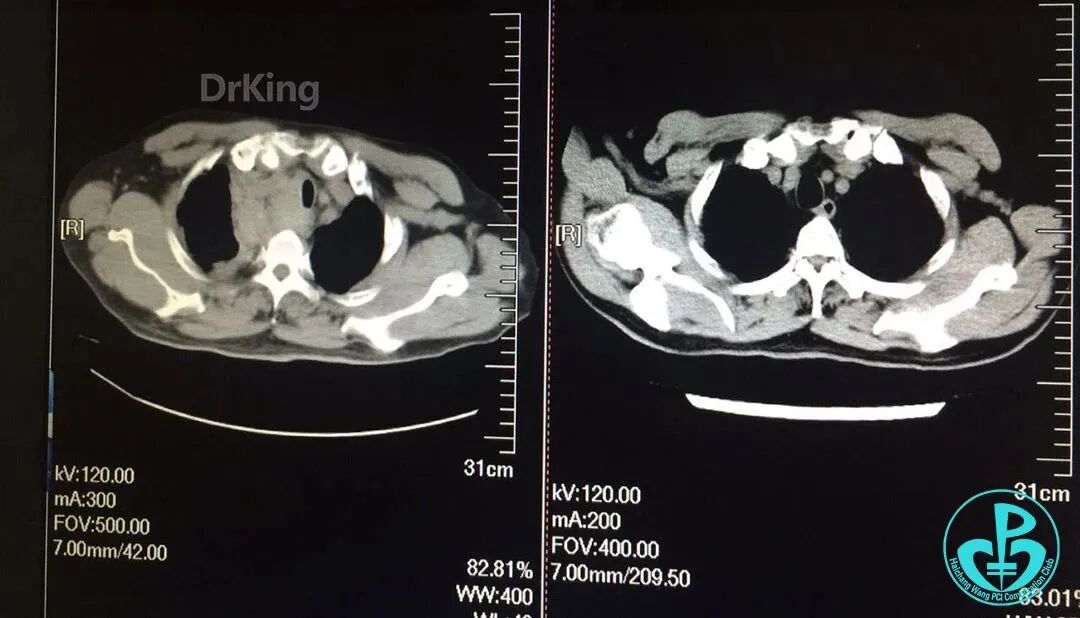

入院前急诊肺CT与术后2小时胸部CT对照,术后发生纵隔血肿。

泥鳅导丝怎么用超滑泥鳅导丝致纵隔血肿,保守治疗血肿吸收_https://www.jmylbn.com_新闻资讯_第13张

主动脉弓层面前后CT对照。